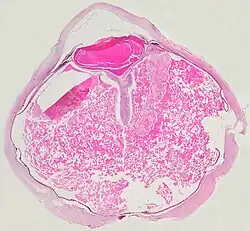

A case of Coats' disease, showing total retinal detachment with subretinal exudate containing cholesterol crystals and a fibrous nodule in the posterior pole

Grossly, retinal detachment and yellowish subretinal exudate containing cholesterol crystals are commonly seen.

A case of Coats' disease, showing total exudative retinal detachment, and subretinal exudate containing cholesterol crystals (H&E)

Microscopically, the wall of retinal vessels may be thickened in some cases, while in other cases the wall may be thinned with irregular dilatation of the lumen.[11] The subretinal exudate consists of cholesterol crystals, macrophages laden with cholesterol and pigment, erythrocytes, and hemosiderin.[12] A granulomatous reaction, induced by the exudate, may be seen with the retina.[13] Portions of the retina may develop gliosis as a response to injury.